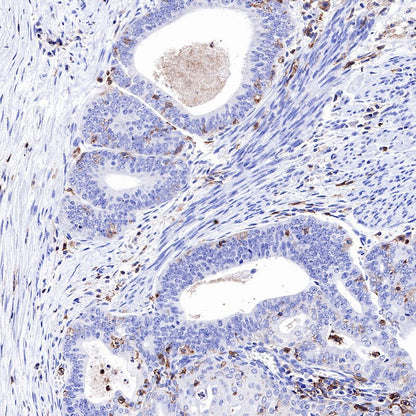

IHC shows positive staining in paraffin-embedded human colon cancer. Anti-CD43 antibody was used at 1/1000 dilution, followed by a HRP Polymer for Mouse & Rabbit IgG (ready to use). Counterstained with hematoxylin. Heat mediated antigen retrieval with Tris/EDTA buffer pH9.0 was performed before commencing with IHC staining protocol.

IHC shows positive staining in paraffin-embedded human endometrial cancer. Anti-CD43 antibody was used at 1/1000 dilution, followed by a HRP Polymer for Mouse & Rabbit IgG (ready to use). Counterstained with hematoxylin. Heat mediated antigen retrieval with Tris/EDTA buffer pH9.0 was performed before commencing with IHC staining protocol.